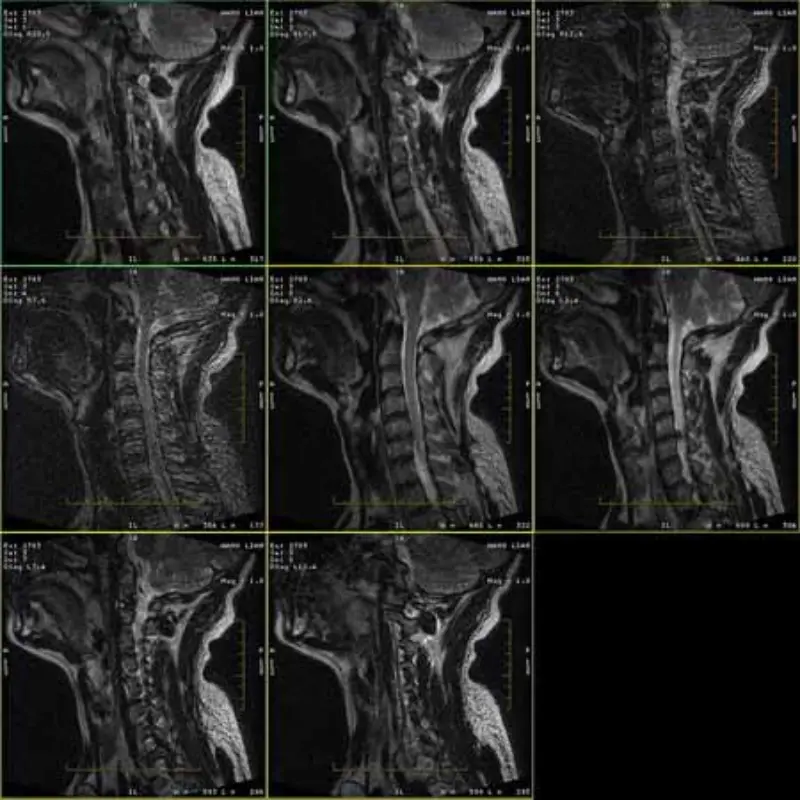

Слике ФРФСЕ и ГРЕ протокола имају духовите и понекад се слике са ниским СНР-ом појављују у једној серији. Али слике СЕ протокола су нормалне.

Молимо погледајте приложене слике.